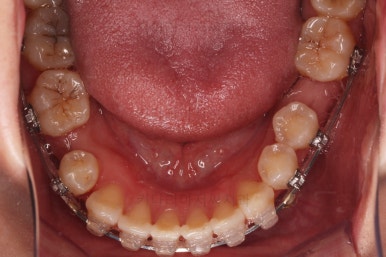

초진 시 입안의 모습입니다.

당장 눈에 띄는 부분은 아래 앞니 사이에 틈새가 있어 치석도 많이 쌓여있는 상황이고요.

윗니-아랫니를 각각 보면 치아가 썩고 부러져 뿌리만 남은 치아가 많이 보입니다.

남은 치아들도 곳곳에 충치가 보이고요.

또 전반적으로 앞니가 앞으로 밀려나와 뻐드러져 있는 모습도 관찰되네요.